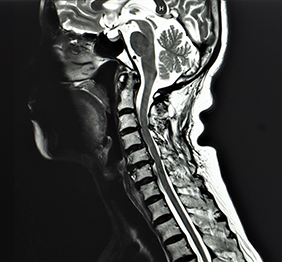

RMN regiune cervicala

Recomandarea pentru IRM regiune cervicală vine in urma identificarii unor anomalii functionale sau atunci cand exista simptome care intereseaza organele sau structurile gatului.